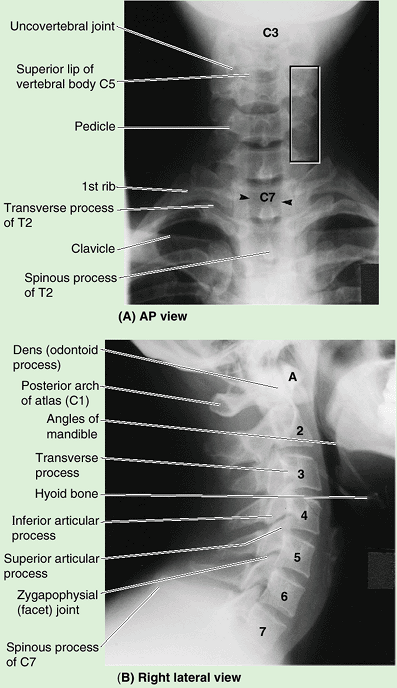

The smallest of the 24 movable vertebrae, the cervical vertebrae are

located between the cranium and the thoracic vertebrae. Their smaller

size reflects the fact that they bear less weight than do the larger

inferior vertebrae. Although the cervical IV discs are thinner than

those of inferior regions, they are relatively thick compared to the

size of the vertebral bodies they connect. The relative thickness of

the discs, the nearly horizontal orientation of the articular facets,

and the small amount of surrounding body mass give the cervical region

the greatest range and variety of movement of all the vertebral regions.

|

Table 4.1. Cervical Vertebraea

||||||||||||||||

|---|---|---|---|---|---|---|---|---|---|---|---|---|---|---|---|---|

![]() |

Figure 4.4. Cranial base and C1 and C2 vertebrae. A. Observe the occipital condyles that articulate with the superior articular surfaces (facets) of the atlas (vertebra C1). B.

The atlas, on which the cranium rests, has neither a spinous process nor a body. It consists of two lateral masses connected by anterior and posterior arches. C and D. The tooth-like dens characterizes the axis (vertebra C2) and provides a pivot around which the atlas turns and carries the cranium. It articulates anteriorly with the anterior arch of the atlas (“Facet for dens” in part B) and posteriorly with the transverse ligament of the atlas (see part B). |

They have large vertebral foramina to accommodate the enlargement of

the spinal cord in this region in relation to the innervation of the

upper limbs. The superior borders of the transversely elongated bodies

of the cervical vertebrae are elevated posteriorly and especially

laterally but are depressed anteriorly, resembling somewhat a sculpted

seat (Table 4.1B).